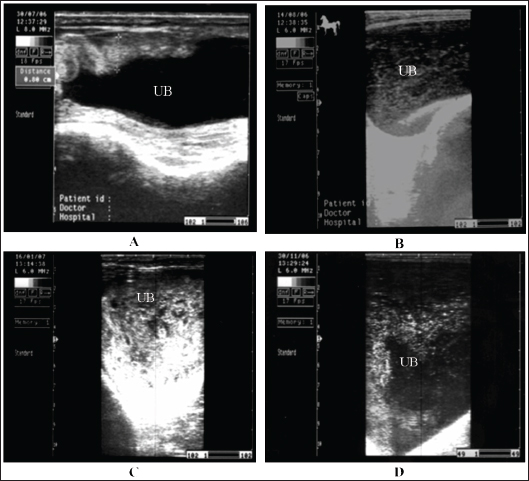

Horses with cystitis show signs of pollakiuria, hematuria, pyuria, stranguria, and urine scalding in the perineum in mares or in front of the hind legs of male equines (Smith, 2015). Usually, females are affected more frequently than males. In cases of cystitis, diffuse or focal thickening and irregularity of the bladder wall are the most common imaged abnormalities detected in horses with diseases, and the urine is usually echogenic to hyperechoic (Le Jeune and Whitcomb, 2014). Staining, arched back, and maiming urination posture for a long time are also observed. Case history and clinical signs are usually diagnostic in most cases. Pronounced thickening of the bladder wall is the most frequently observed finding on ultrasonography of the bladder, and the urine is more echogenic (Zakia et al., 2021). In addition, fibrin strands are imaged in equines with intense cystitis, whereas in healthy animals, the urinary bladder wall appears echogenic and the urine appears anechoic with hyperechoic particles (Fig. 18). Antimicrobials are prescribed to eliminate infections, and the verification of the antimicrobial sensitivity of the causative agent is crucial. Recurrence is common unless therapy is continued for a period of 7–14 days. Repeated urine culture at least once during treatment and within 7–10 days after treatment should be performed to estimate the success or failure of therapy (Reed et al., 2004).

Fig. 18. A sonogram of horses suffering from cystitis showed. Images A and B were obtained from the transrectal window using an 8-MHz linear transducer. Corrugation of the bladder wall (A) and hyperechogenicity of the bladder contents with distal acoustic enhancement (B). Images C and D were obtained from the transrectal window using a 6-MHz transducer. Notice hyperechogenicity of the bladder contents, which leads to acoustic enhancement (C and D). UB=urinary bladder.

Fig. 19. Sonogram of horses with urine retention showed. In images A and B, the urinary bladder appears distended. In image C, the bladder collapses after catheter application. These sonograms were obtained from the transrectal window using a 6-MHz transducer. Image A was taken transcutaneously using a 3.5-MHz sector probe, while images B and C were taken transrectally using a 6.0-MHz linear transducer.

Horses suffering from urine retention also showed severe restlessness with failure in urinate testing. History and clinical manifestations are usually diagnostic. The urinary bladder was imaged, revealing a marked distension with echogenic urine causing distal enhancement and hyperechoic sediment ventrally in the bladder. The bladder wall is normal unless concurrent cystitis is present (Abu-Seida and Shamaa, 2020). After catheter application, the urinary bladder returns to normal size, and the wall will also be normal (Fig. 19). Management of cystic calculi is performed by surgical removal of the calculi and correction of any bladder perforation, if present. Ultrasound-guided, transcutaneous right kidney nephrostomy has been reported in a horse with ureteral calculi for the purpose of short-term diversion of urine (Duesterdieck-Zellmer, 2007). Surgically, sub-ischial urethrotomy may be conducted under epidural anesthesia (Abu-Seida and Shamaa, 2020).